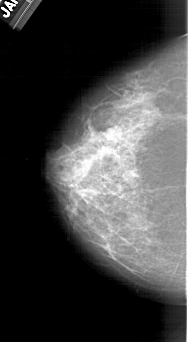

A_1382_1.RIGHT_MLO

RIGHT_MLO LINES 5866 PIXELS_PER_LINE 2911 BITS_PER_PIXEL 12 RESOLUTION 43.5 OVERLAY

FILE: A_1382_1.RIGHT_MLO.OVERLAY

TOTAL_ABNORMALITIES 1

ABNORMALITY 1

LESION_TYPE CALCIFICATION TYPE PLEOMORPHIC DISTRIBUTION CLUSTERED

ASSESSMENT 4

SUBTLETY 3

PATHOLOGY BENIGN

TOTAL_OUTLINES 1

BOUNDARY